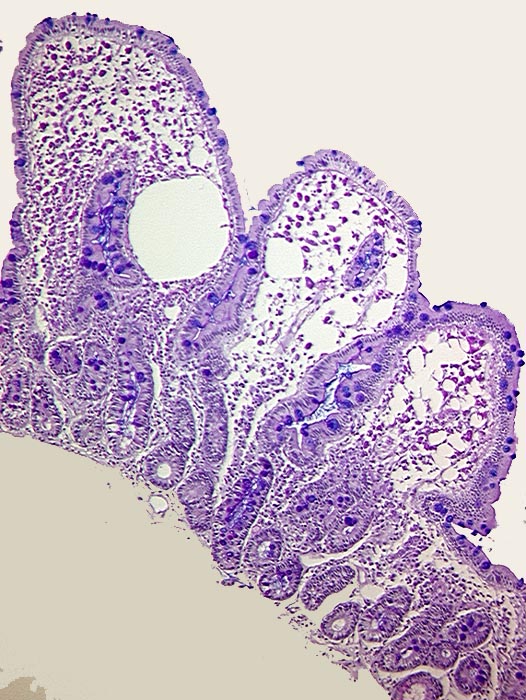

AP/ Morbus Whipple

Morbus Whipple

Dünndarm

Pathologischer Befund